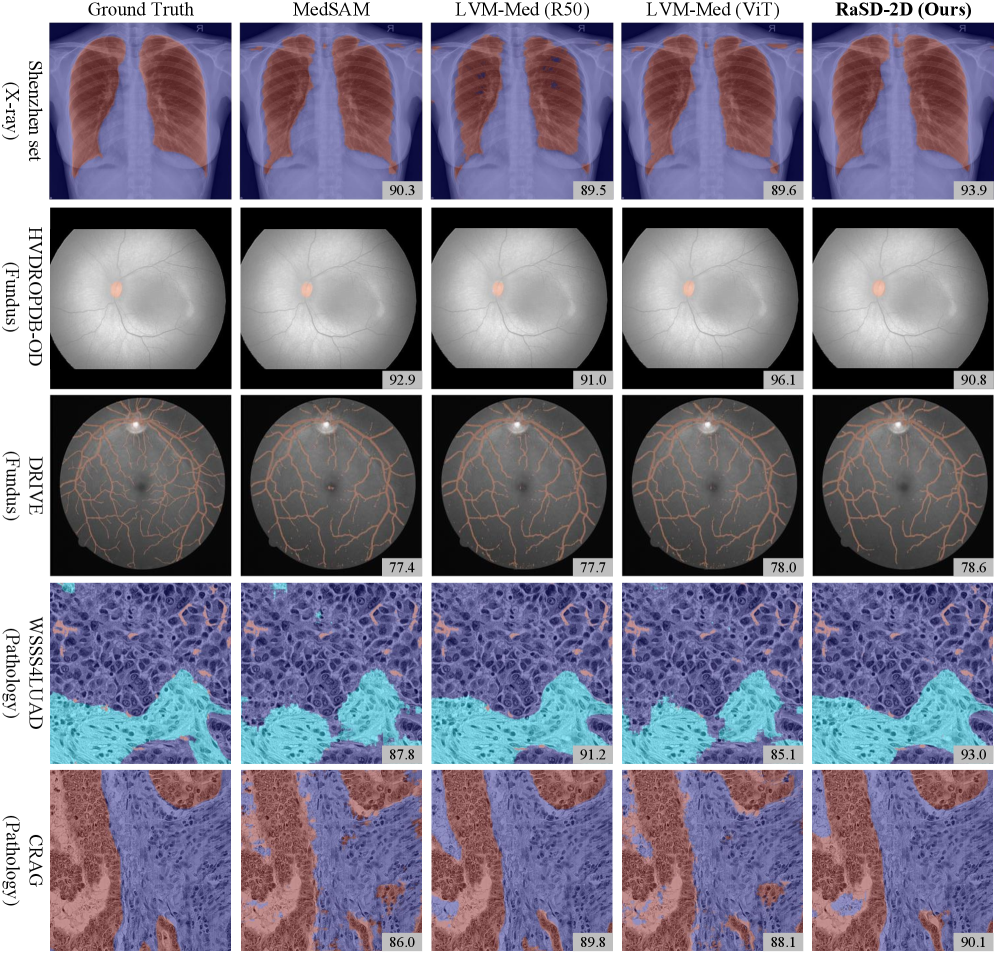

Our RaSD also brings strong and consistent performance improvement across multiple fundus image tasks. We conducted experiments on five segmentation and three classification tasks and benchmarked RaSD against three SOTA MIFMs, including LVM-Med (R50), LVM-Med (ViT), and MedSAM, and a randomly initialized model (“Scratch”).

RaSD demonstrates strong capability in retinal tissue segmentation across multiple datasets (Fig. 4 a–e). On the STARE dataset (b), it achieved an 80.4% Dice, surpassing LVM-Med (R50) by 0.3%, underscoring its ability to capture fine-grained, discriminative features essential for intricate vessel structures. On vessel segmentation (DRIVE, a), RaSD attained an 86.7% Dice, remaining within 1.5% of the best-performing methods. Its robust performance further extends to optic disc and ridge segmentation (HVRODPDB-BV, HVRODPDB-OD, HVRODPDB-RIDGE; c–e), where it consistently outperformed scratch models, confirming its generalizability across diverse segmentation challenges in fundus imaging. These results highlight RaSD’s ability to learn fine-grained and dense structural representations from synthetic data, enabling competitive performance in retinal segmentation tasks without reliance on real-image pre-training.

2.5.2 Fundus image Classification

RaSD also demonstrates competitive performance on retinal disease classification tasks (Fig. 4 f-g). Across both DRAC and IDRiD datasets, RaSD consistently outperforms the from-scratch baseline, achieving statistically significant improvements of 3.9% and 3.2%, respectively, indicating that synthetic pre-training provides effective initialization for fundus image classification. Despite being trained exclusively on synthetic data, RaSD exhibits robust transferability across retinal datasets, enabling consistent performance gains without relying on large-scale real-image pre-training.

2.6 RaSD delivers superior pathology segmentation

RaSD-2D demonstrates strong and generalizable performance across a diverse spectrum of pathology segmentation tasks (Fig. 4 h-p). To comprehensively evaluate our approach, we benchmarked it against four key baselines, including SOTA general-purpose foundation model LVM-Med (R50), LVM-Med (ViT), and MedSAM and a SOTA model specialized for pathology, PathSegmentator[chen2025segment]. Our RaSD outperforms all general-purpose foundation models (LVM-Med R50/ViT and MedSAM) on four out of nine datasets (i, l, n, p), convincingly validating its superior representation learning capability. Our RaSD also achieves the highest Dice scores on the CoCaHis (i) and Janowczyk (l) datasets, surpassing the pathology-specific model PathSegmentor by 5.3% and 8.1% respectively. This demonstrates that our synthetic data pre-training RaSD is not only comparative with real-image pre-trained models but can even exceed the performance of modality-specific models in some tasks. These results show that learning through randomized synthesis and disentanglement provides a powerful and scalable pathway toward building high-performing foundation models without the dependency on large-scale real data.